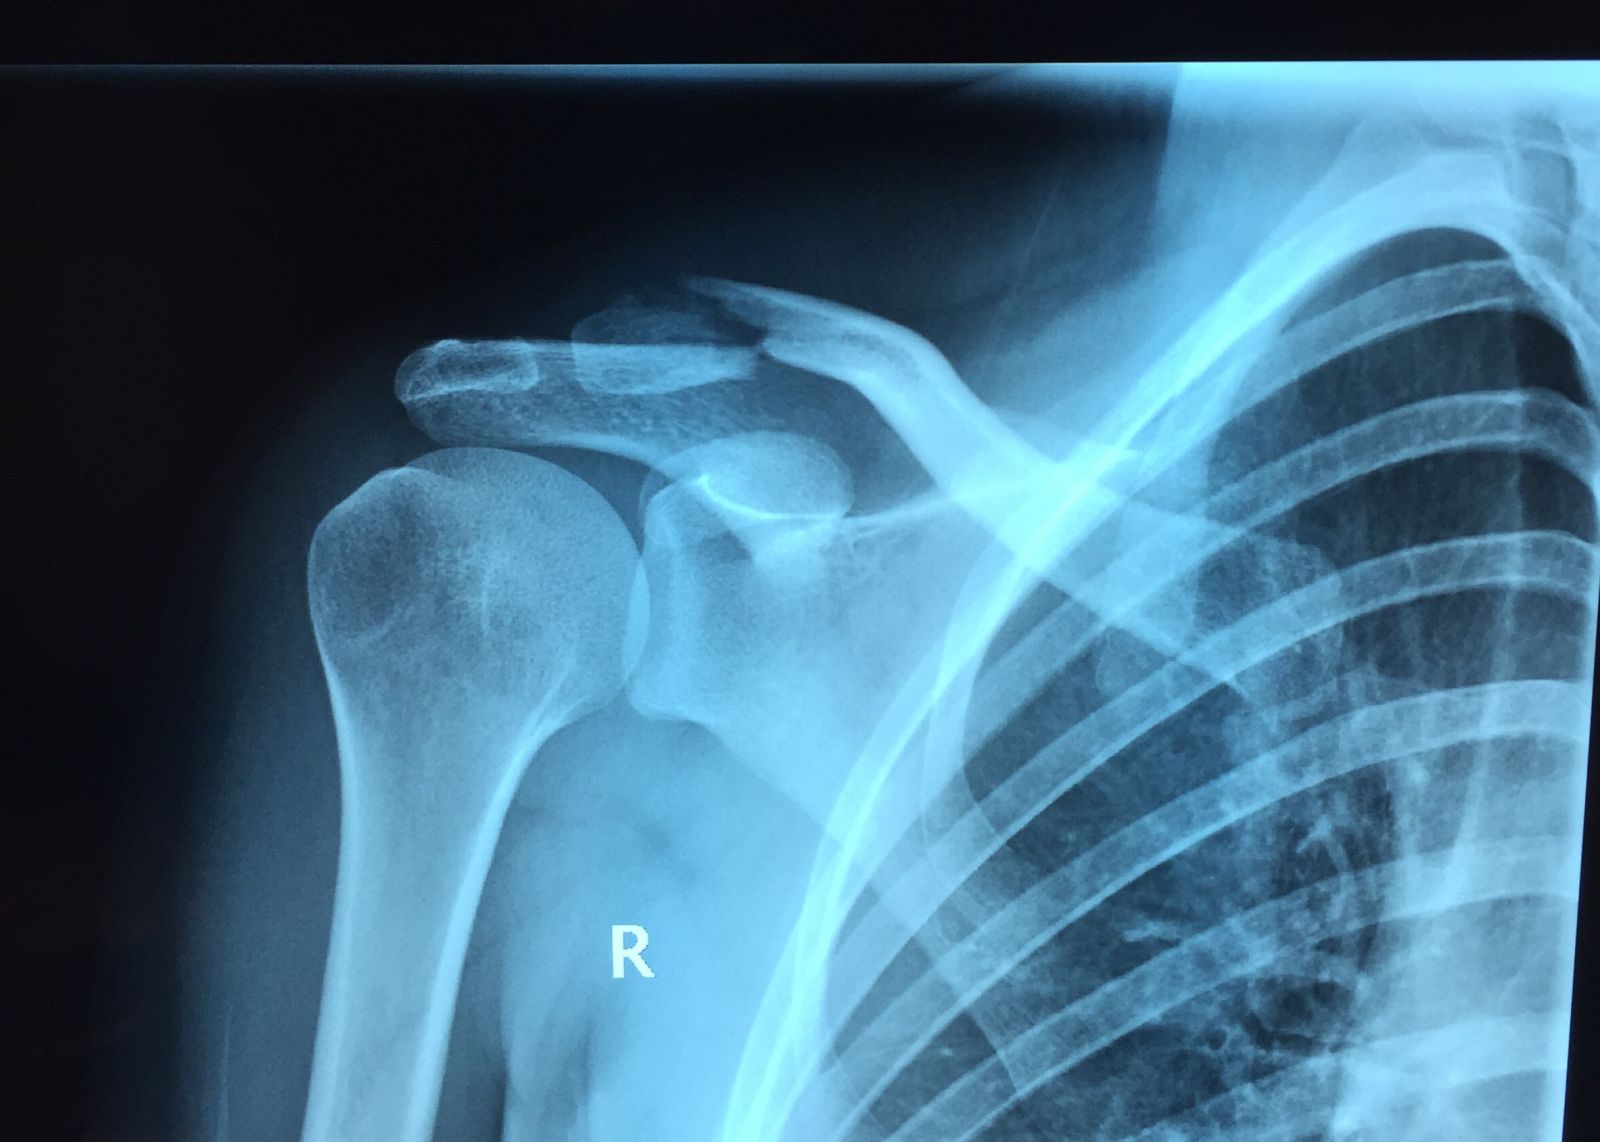

Σε περιπτώσεις μεγάλης συντριβής και παρεκτόπισης, είναι προφανές ότι, υπάρχει κίνηση μεταξύ των κατεαγότων άκρων και δεν μπορεί να εξασφαλισθεί ένα «σταθερό περιβάλλον» που θα επιτρέψει το σχηματισμό πώρου, πέραν του άλγους και της δυσχέρειας κινήσεων. Στις περιπτώσεις αυτές, η θεραπεία του κατάγματος είναι χειρουργική. Τέτοιες περιπτώσεις, περιλαμβάνουν κυρίως τα παρεκτοπισμένα κατάγματα του μέσου και έξω τριτημορίου της κλείδας.

Τα κατάγματα του έξω τριτημορίου της κλείδας αποτελούν ιδιαίτερη κατηγορία διότι,συχνά συνοδεύονται από συνδεσμικές βλάβες (βλέπε εξάρθρημα ακρωμιοκλειδικής). Στις περιπτώσεις αυτές, πέραν της οστεοσύνθεσης, πραγματοποιείται και ανακατασκευή των τραυματισμένων συνδέσμων. Στην περίπττωση αυτή τροποποιείται ανάλογα και το πρόγραμμα μετεγχειρητικής αποκατάστασης.

Προεγχειρητικά

Προεγχειρητικά